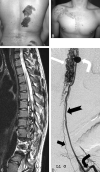

Fig 3.

A, Faint diffuse capillary stain covering asymmetrically thickened soft tissue of the back and scoliosis. B, Sagittal T2-weighted MR image demonstrates a large area of abnormal heterogeneous tissue and signal-intensity void involving the paraspinal muscles, thecal sac, and adjacent lumbar vertebrae. Some fatty thickening and flow voids are also seen in the retroperitoneum. There is some loss of anterior height of the lumbar vertebrae with irregular contour, dehydration of the intervertebral disks, and kyphosis. C, Selective angiogram of the right L3 segmental artery demonstrates arterial dilation with extensive supply to the paravertebral AVM, centered within the paraspinal musculature. D, Selective study of the artery of Adamkiewicz (left T11) demonstrates a pial arteriovenous fistula at the L2 level.